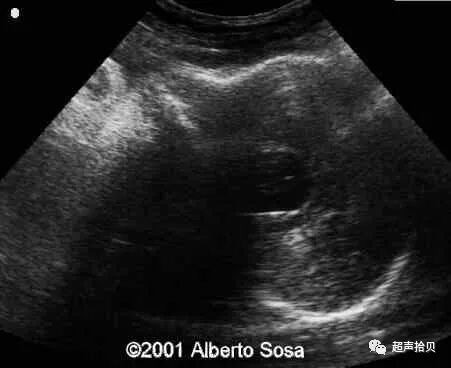

图4:图4A,25次妊娠时获得的横向声像图。 病变最初被诊断为蛛网膜

囊肿(C)伴有出血(H)。 B,妊娠26孕妇的产前MRI T2加权横向图像显示硬脑膜窦性畸形(D)合并血栓形成(T)